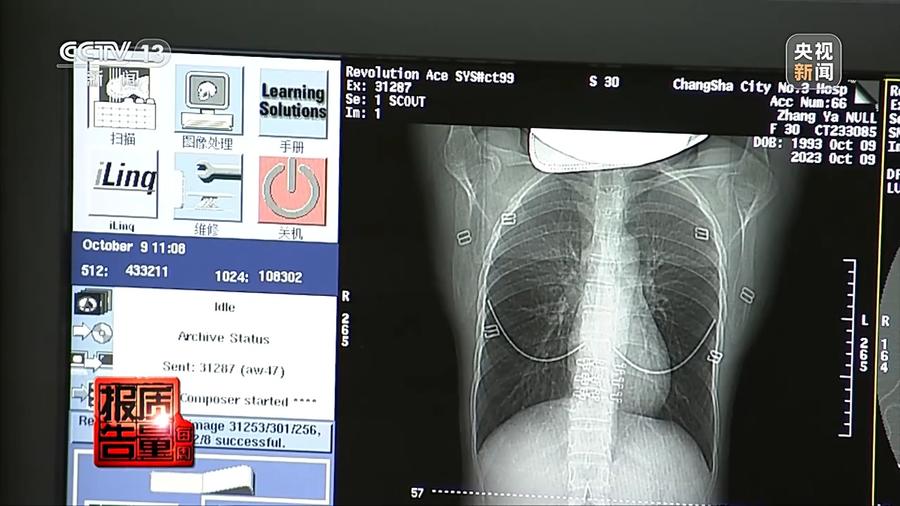

前不久,长沙市第三医院急诊科来了一位患者,他因呼吸困难和咳嗽前来就诊。急诊医生为患者开具了胸部CT检查的申请,经过多维度CT照映成像,发现这位患者的双肺呈现大面积对称性的白色磨玻璃影,也就是我们俗称的——白肺。医生建议患者入院治疗,但患者表示自己是一位游客,只在长沙停留两天,于是开了些消炎药就离开了医院。放射科医生对此感到非常疑惑,因为白肺通常只会出现在老年人群体,还有部分新冠疫情期间的重症患者,而这位患者非常年轻,怎么会突然出现这么严重的“白肺”表征呢?

长沙市第三医院放射影像科主任 张秀萍:他就是双肺出现对称性、弥漫性的磨玻璃密度影,可以看到他肺部的肺疮,双肺出现对称性的密度增高影,这白色的一大片,从上肺到下肺就都有。